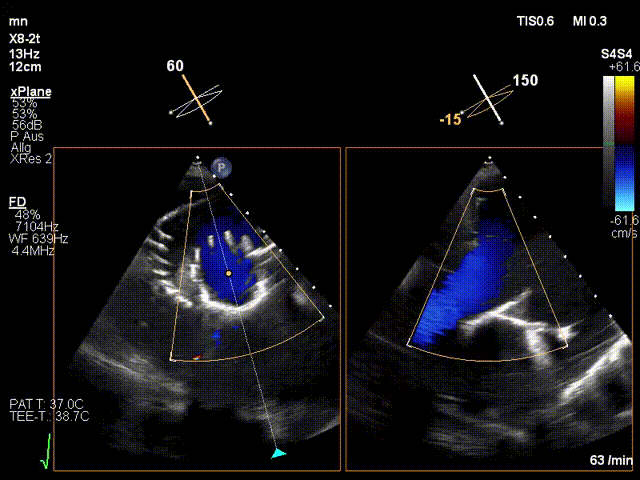

手術(shù)在全麻狀態(tài)下進行。在加拿大圣保羅醫(yī)院的Anson Cheung教授的指導(dǎo)參與下,術(shù)者采用經(jīng)右側(cè)頸靜脈入路的方式將輸送器送入患者心臟內(nèi),在TEE及DSA引導(dǎo)下調(diào)整輸送器頭端角度,使得輸送器與三尖瓣瓣環(huán)平面垂直。在輸送器進入右心室后釋放室間隔錨定裝置,而后釋放瓣葉夾持件(2個耳片結(jié)構(gòu))成垂直狀態(tài)。在TEE及DSA確定夾持件固定至三尖瓣葉根部且位于右室側(cè)后釋放人工瓣心房側(cè)盤片。隨后調(diào)整瓣膜同軸性以及室間隔錨定件位置(貼合室間隔),前推藏針管并固定,進而釋放室間隔錨定裝置,并再次確認瓣膜位置、穩(wěn)定性及同軸性,合攏輸送鞘后撤出輸送器,完成LuX-Valve Plus人工三尖瓣瓣膜的植入。

LuX-Valve Plus經(jīng)血管三尖瓣置換系統(tǒng)本次“出海”圓滿完成,術(shù)后Jörg Hausleiter教授對LuX-Valve Plus經(jīng)血管三尖瓣置換系統(tǒng)的器械性能和治療效果大為稱贊,認為LuX-Valve Plus的手術(shù)體驗非常好。術(shù)后即刻超聲顯示三尖瓣反流消失,血流動力學(xué)改善顯著,患者恢復(fù)快。Anson Cheung教授也肯定了LuX-Valve Plus術(shù)中操作的便捷性,認為LuX-Valve Plus容錯率高,對術(shù)中影像的依賴較小,后期希望可以更多的應(yīng)用LuX-Valve Plus三尖瓣置換系統(tǒng)于臨床實踐,讓更多的三尖瓣重度反流患者盡早獲益,改善預(yù)后。